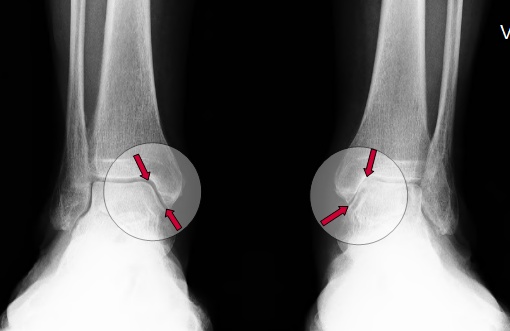

Die Betroffenen beschreiben den Fußexperten der Gelenk-Klinik häufig im Gespräch Fußschmerzen bei Belastung über dem Fußinnenrand im Bereich des Innenknöchels. Zum Teil lokalisieren die Patienten die Beschwerden um den Knöchel herum bis in den Unterschenkel reichend. Häufig wird auch eine Knöchelschwellung beschrieben, die innen und außen auftreten kann. Die Schmerzintensität ist dabei abhängig vom Erkrankungsstadium und der Lebensweise der Patienten.

Regelmäßig geben Patienten nur einen Belastungsschmerz am Fußaußenrand vor dem Außenknöchel an. Neben diesen konkreten Beschwerden klagen viele Frauen über eine verminderte Gehstrecke, leichte Ermüdbarkeit und Schwäche im Fuß.

Tritt der Patient nur einseitig auf dem Fuß auf, kann das ein Hinweis auf die Erkrankung sein. Es kann aber auch bedeuten, dass sich ein bereits vorhandener Senkfuß einseitig verschlechtert hat. Der Arzt achtet zudem auf vorhandene Fehlstellungskomponenten, Schwellungen, Druckschmerzhaftigkeit über dem Sehnenverlauf oder auch über dem außen liegenden Sinus tarsi.

Eine Ultraschalluntersuchung zeigt direkt die Verdickung oder den Riss (Ruptur) der Tibialis-posterior-Sehne.